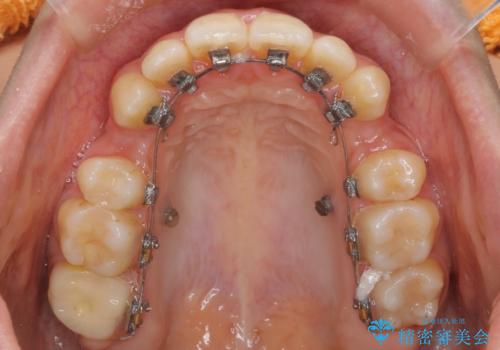

- 矯正装置

- ハーフリンガル

裏側の装置は、汚れが溜まりやすく虫歯や歯周病にかかりやすいというリスクが増加します。

ワイヤー矯正の注意事項(リスク・副作用など)

- 治療中は歯磨きがしにくくなるため、虫歯や歯周病になりやすくなります